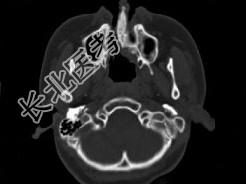

- 单项选择题男,14岁, 脓涕,头痛, CT检查如图,最可能的诊断是 ( )

A、右上颌窦炎

B、腭裂,右上颌窦炎

C、颅面骨发育不良

D、上颌骨骨结核合并瘘道形成

E、上颌骨骨脓肿并瘘道形成